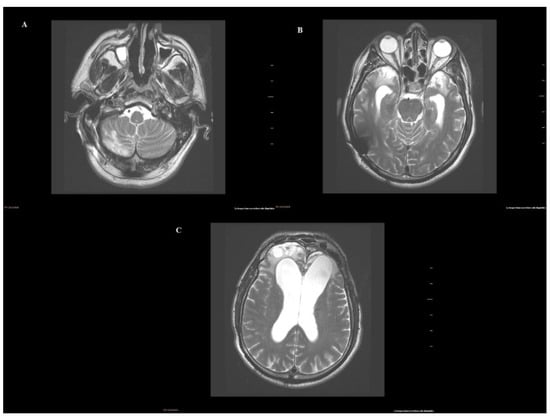

2. Case Report

2.1. Medical Background